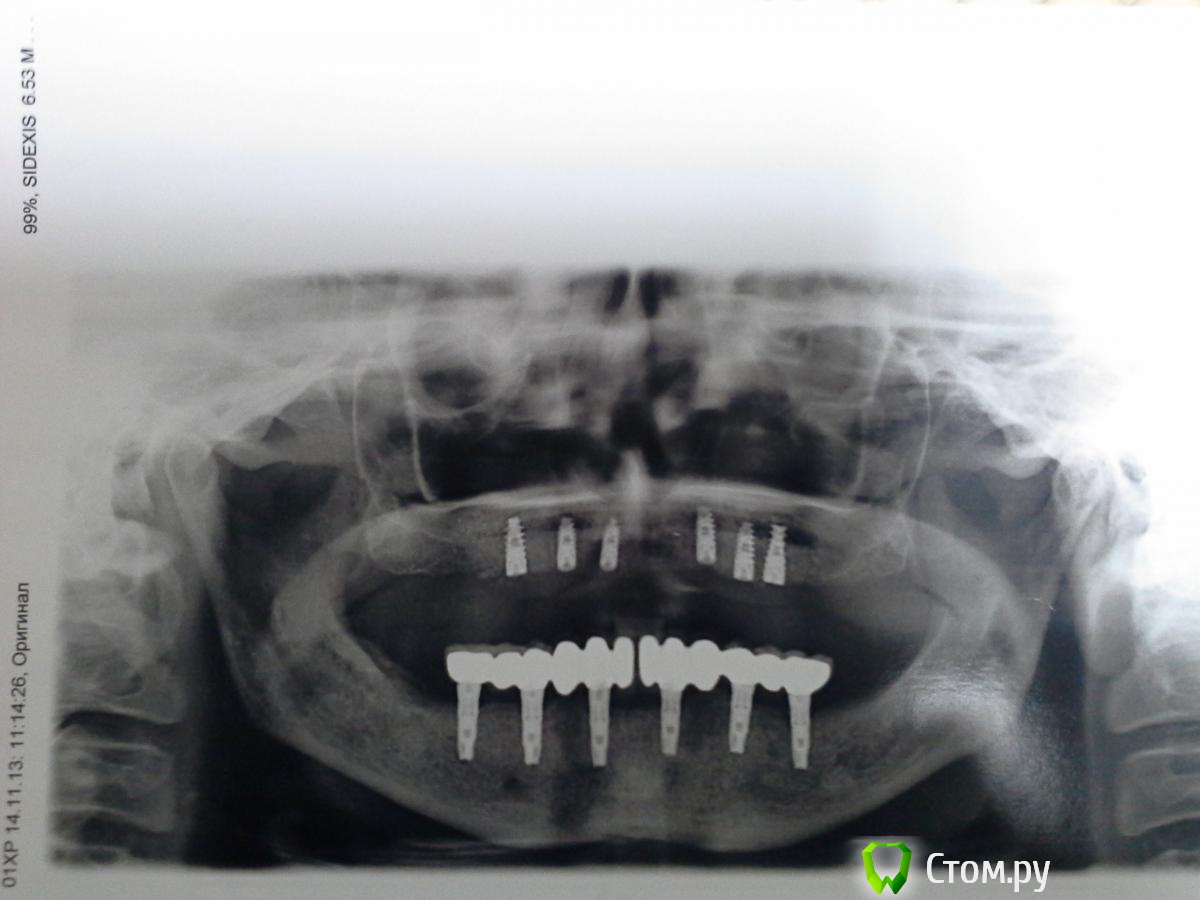

Magomed Опубликовано 3 сентября, 2014 Поделиться Опубликовано 3 сентября, 2014 (изменено) работу делал год. в.ч.удалил 8 з. низ 6 з. в.ч. каркас фрезеров. низ литьё. Изменено 3 сентября, 2014 пользователем Magomed Ссылка на комментарий

anvladd Опубликовано 4 сентября, 2014 Поделиться Опубликовано 4 сентября, 2014 смущают консоли на верху. Ссылка на комментарий

Bier Опубликовано 4 сентября, 2014 Поделиться Опубликовано 4 сентября, 2014 смущают консоли на верху.чем? есть же формула, уверен они вписываются в нее. Ссылка на комментарий

ILGAMSA Опубликовано 4 сентября, 2014 Поделиться Опубликовано 4 сентября, 2014 смущают консоли на верху.По ITI если протяженность протяженность конструкции не менее 30мм, то длина консоли может достигать... внимание(!)... 15мм! 1 Ссылка на комментарий

Bier Опубликовано 4 сентября, 2014 Поделиться Опубликовано 4 сентября, 2014 влияет не количество опор, а передне-задний размер. между передним и задним имплантатом. 1 Ссылка на комментарий

Magomed Опубликовано 5 сентября, 2014 Автор Поделиться Опубликовано 5 сентября, 2014 Здравствуйте, сколько прошло от момента имплантации верх и них и от протезирования верх и низ?низ 8 мес. верх 2 нед. протезирования Ссылка на комментарий

Magomed Опубликовано 5 сентября, 2014 Автор Поделиться Опубликовано 5 сентября, 2014 (изменено) и мне каж.консоль здесь не навредит. Изменено 5 сентября, 2014 пользователем Magomed Ссылка на комментарий